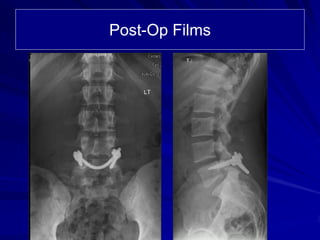

The document details the case of a 25-year-old major league baseball player diagnosed with multiple pars and pedicle fractures in the lumbar spine after experiencing back pain due to pitching. Conservative treatments failed, leading to a proposed surgical strategy involving laminotomy, spinal fixation, and fusion to address the fractures and alleviate nerve root entrapment. The player has additional comorbidities and underwent thorough imaging to guide the surgical approach.